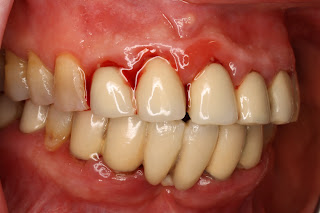

In queste due immagini osserviamo un paziente con parodontite grave di anni 27; sono evidenti notevoli depositi di taratro sopra e sotto gengivale; un drammatico quadro di infiammazione dei tessuti gengivali, perdita delle papille e recessioni dei margini gengivali; il paziente presenta anche malocclusione che ha aggravato il quadro clinico parodontale; si tratta di un biotipo sottile in cui il riassorbimento osseo e' avvenuto a tutto spessore determinando le recessioni del margine gengivale; si nota la fotografia in basso a distanza di circa 25 giorni dalla terapia igienica e dalla motivazione all'igiene orale; i tessuti persi non potranno essere recuperati ma il paziente ha acquisito una giusta tecnica di igiene orale che gli consentira', se mantenuta nel tempo unitamente a controlli costanti in studio, di bloccare la progressione della malattia.

Purtroppo le lesioni del parodonto superficiale e profondo possono essere prodotte anche da restauri protesici non congrui; in questo caso osserviamo come l'applicazione di una protesi fissa abbia provocato un notevole processo infiammatorio dei tessuti parodontali: si notano sanguinamento elevato, invasione dell'ampiezza biologica, violazione degli spazi interdentali con impossibilita' all'utilizzo degli strumenti per l'igiene orale quotidiana come filo interdentale e scovolino; in questi casi il risanamento dei tessuti parodontali non puo' prescindere dal rifacimento di una protesi fissa correttamente eseguita;